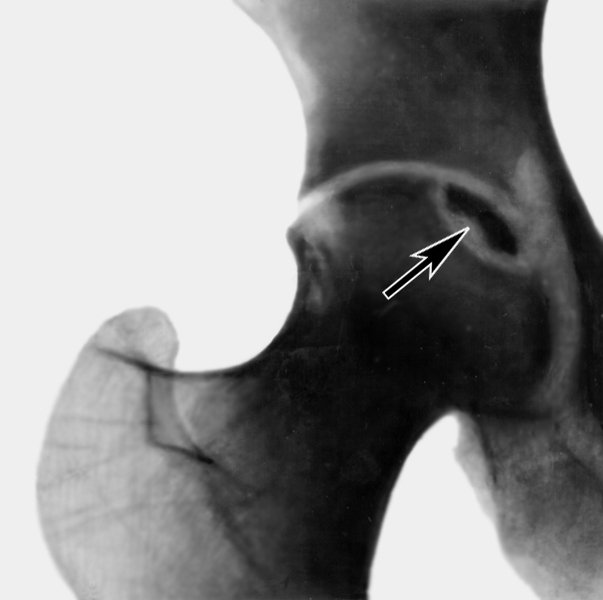

При остеонекрозе тазобедренного сустава боль локализуется в области паха, отдавая в ягодицы и бедра. Со временем наблюдается ограничение подвижности и развитие хромоты. Асептический некроз головки бедренной кости считается особенно сложным заболеванием.

Рентгенография — первый метод, который врач применяет для определения причин болей в суставах. Этот простой способ позволяет получить изображение костей и выявить начальные изменения на ранних стадиях. В дальнейшем рентген помогает отслеживать динамику заболевания.